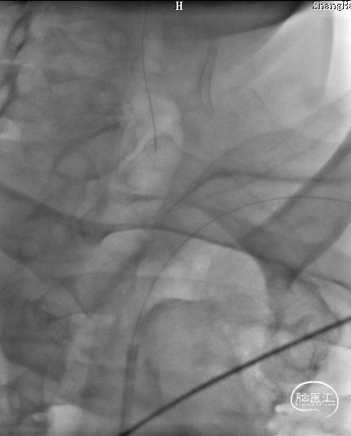

DSA:LSub。

DSA:L-CCA。

沿0.018*300cm 外周导丝送入6*40 外周球囊送至左侧锁骨下动脉狭窄处,压力泵逐渐加压到6atm。

撤出球囊后见残余狭窄40%。

再次沿0.018*300cm 外周导丝送入6*40 外周球囊达LSub狭窄部位,压力泵逐渐加压到8atm,见残余狭窄20%。

造影见LV闭塞,立即沿0.014*200cm 通桥北斗SS™神经血管导丝置入3mm*16mm 药物球扩支架至LV1。

压力泵逐渐加压球扩支架到8atm, 支架打开良好,造影示残余狭窄0%。

双侧锁骨下动脉造影见椎动脉、基底动脉血流通畅,远端未见栓塞表现。